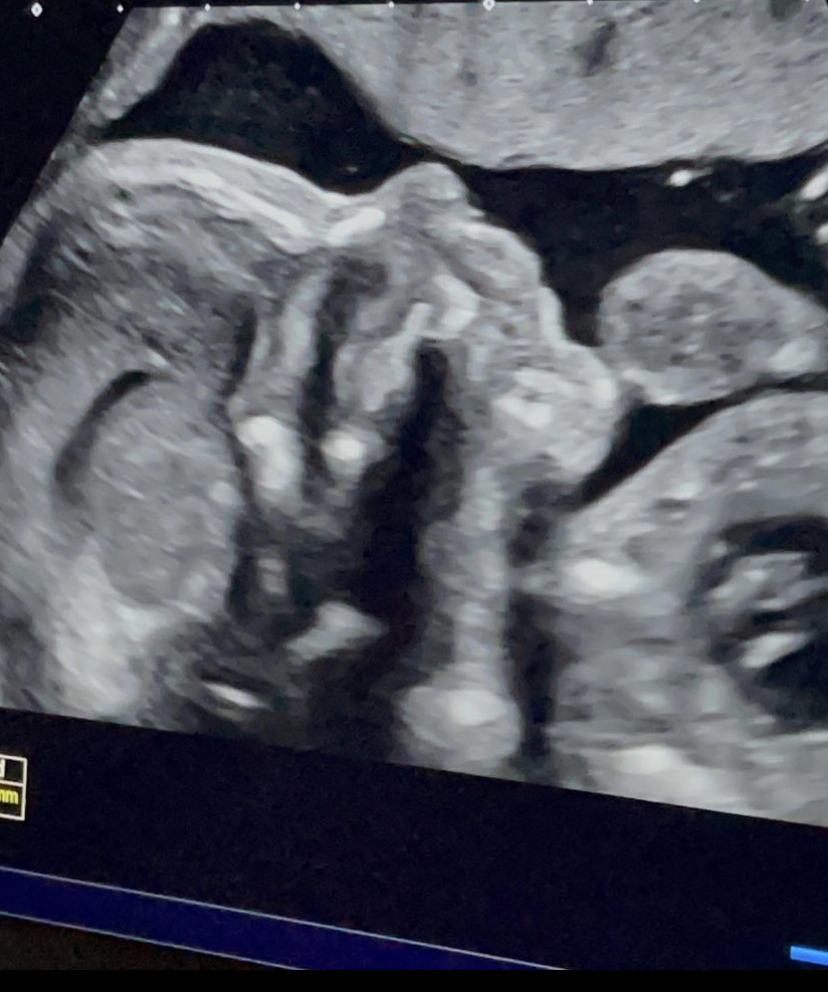

A boa nova foi anunciada esta quinta-feira pelo piloto de motociclismo, nas redes sociais. “As nossas vidas seguem agora com uma companhia especial ❤️ O cargo que durará a nossa vida inteira, a de sermos pais“, revelou Miguel Oliveira que está na Áustria a competir, acrescentando na legenda das imagens publicadas que vão ser pais de uma menina: “Ansioso por te conhecer filhota“.